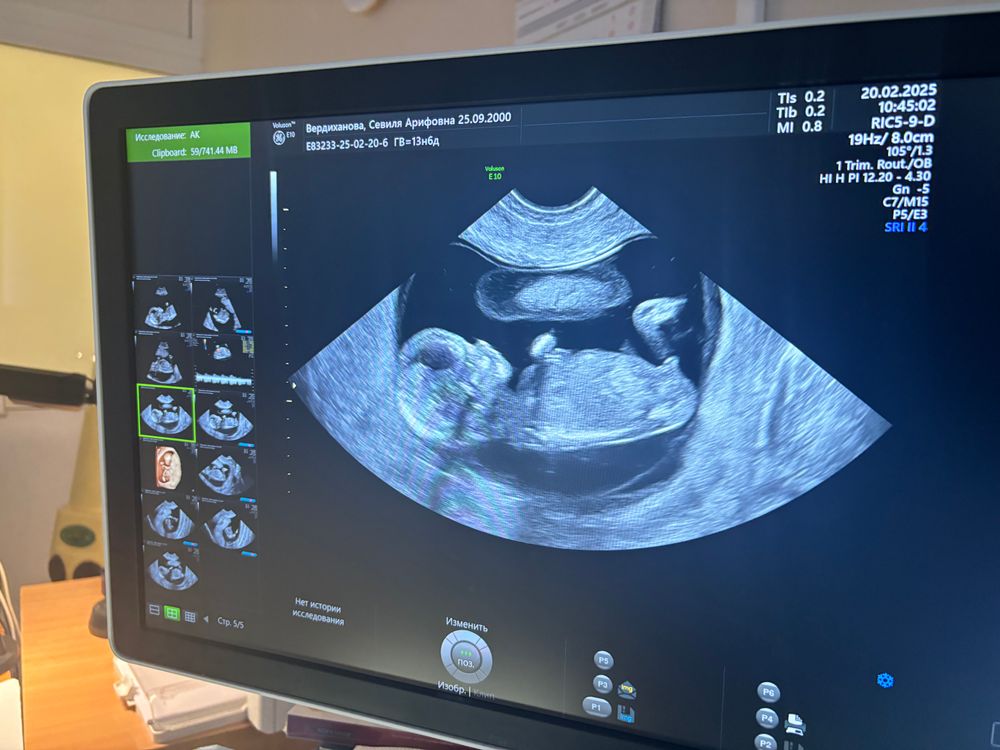

13 неделя

20.02.2025

Конечно это мальчик, поздравляю ❤️

Мальчик🩵

Мальчик)

Мальчик

Мальчик или девочка Скоро гендер-пати🩷💙